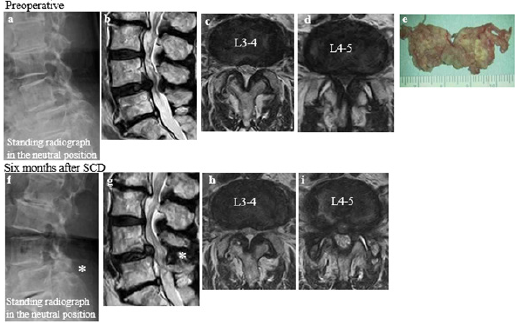

Figure 1: (cited from [8]) A case requiring reoperation after Semi-Circumferential Decompression (SCD, a midsagittal to bilateral microscopic decompression) at L4-5 (Table 3, Case 6). The hypertrophied ligamentum flavum at L4-5 (b, d) had been completely removed (e) with maximal preservation of the facet joints (i) and spinous processes (f, g asterisk ≤10mm between the processes). Compensating flexion as a pain-relieving posture (a) was improved after SCD with developed lumbar lordosis (f), which caused the ligamentum flavum hypertrophy and symptomatic LSS at L3-4 (b, c, g, h).

The microscopic decompression method used, semicircumferential decompression (SCD), features en-bloc removal of the degenerative ligamentum flavum and involves minimal damage to the facet joints and the spinal processes [5,8,17]. After partial resection of the spinal processes of L4 and L5, holding ≤10mm between the two processes, decompression was performed midsagittal to bilateral. Bilateral nerve roots were decompressed from bony entrapment. In addition, neural compression exerted by the epidural membrane and periradicular fibrous tissues were relieved by releasing these tissues from the dura [17]; (Figure 1).

During follow-up, six patients (6.7%; one male and five females) required reoperations. Four patients suffered radiculopathy due to degeneration at the decompressed L4-L5 level: foraminal stenosis (one patient), intraforaminal disc herniation (one patient), and juxta facet cyst (two patients). The remaining two patients suffered leg symptoms due to stenosis at L3-L4 (Figure 1; [8]). The reoperation rate did not differ between males and females (Table 4, P=0.43).